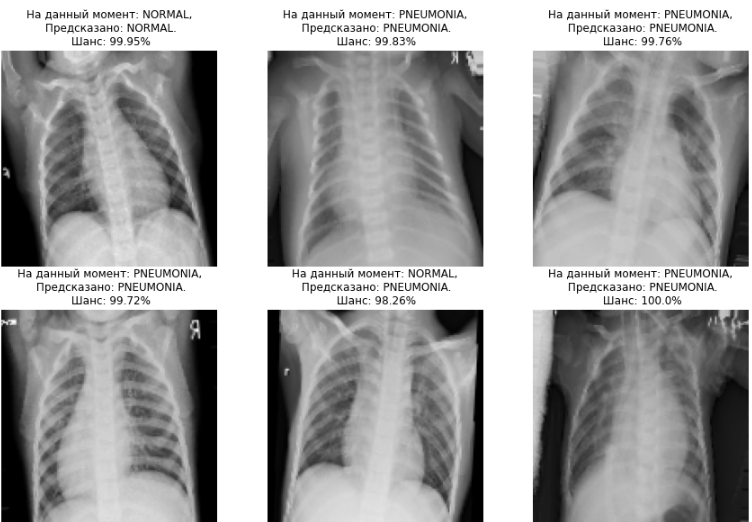

1. Тестирование

2. Вывод результатов